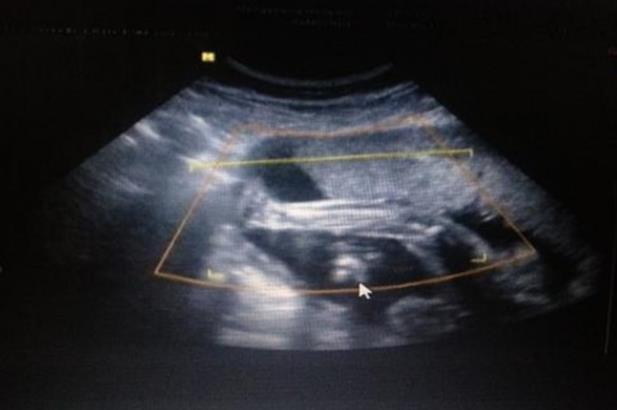

IVF是体外受精-胚胎移植的简称。具体过程是把女方的卵子和男方的精子取出体外。经过优化处理后,在体外完成受精,将胚胎放回女性子宫。对于想做试管婴儿的夫妇来说,首先要在初诊时明确做试管婴儿的指征,自身情况是否适合做试管婴儿。另外,你还要准备好夫妻双方的身份证和结婚证备案。报告出来后,生殖专家会根据检查结果和患者的实际情况制定促排卵方案,然后根据拟定的方案和女方的月经周期安排后续的就医时间。